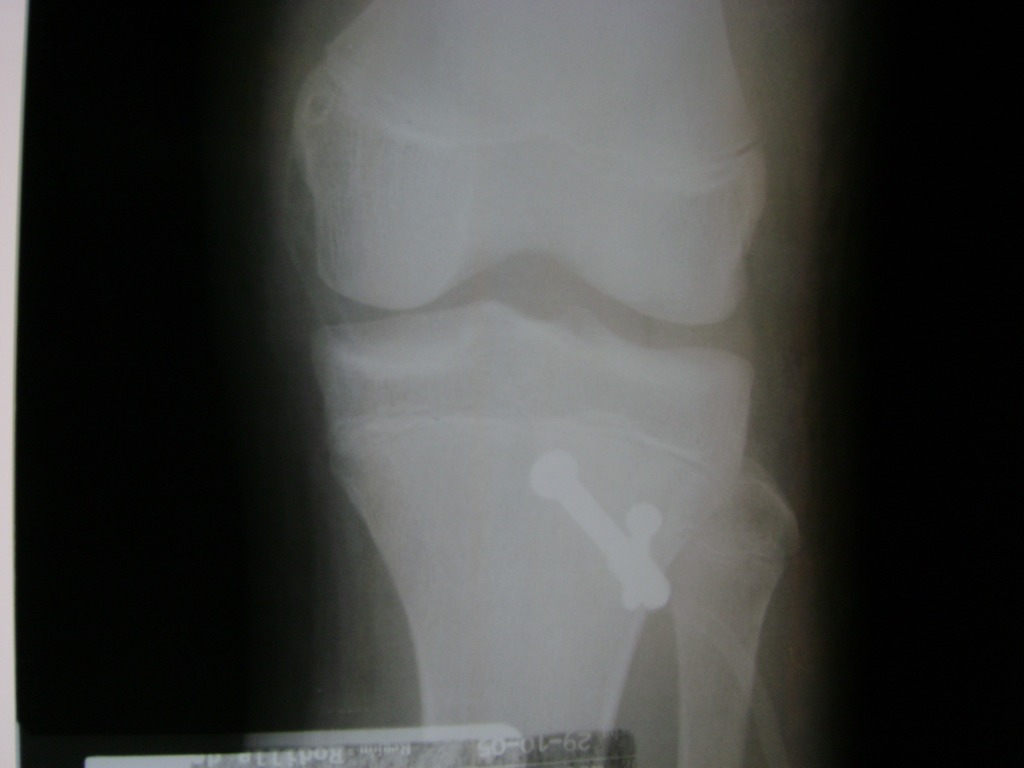

Cirugias en El Salvador - Rodilla

La artroscopia de rodilla es un cirugía en el cual la estructura interna de la articulación es examinada ya sea para realizar un diagnostico o para realizar un tratamiento, este procedimiento se realiza utilizando un instrumento parecido a un pequeño tubo llamado artroscopio.